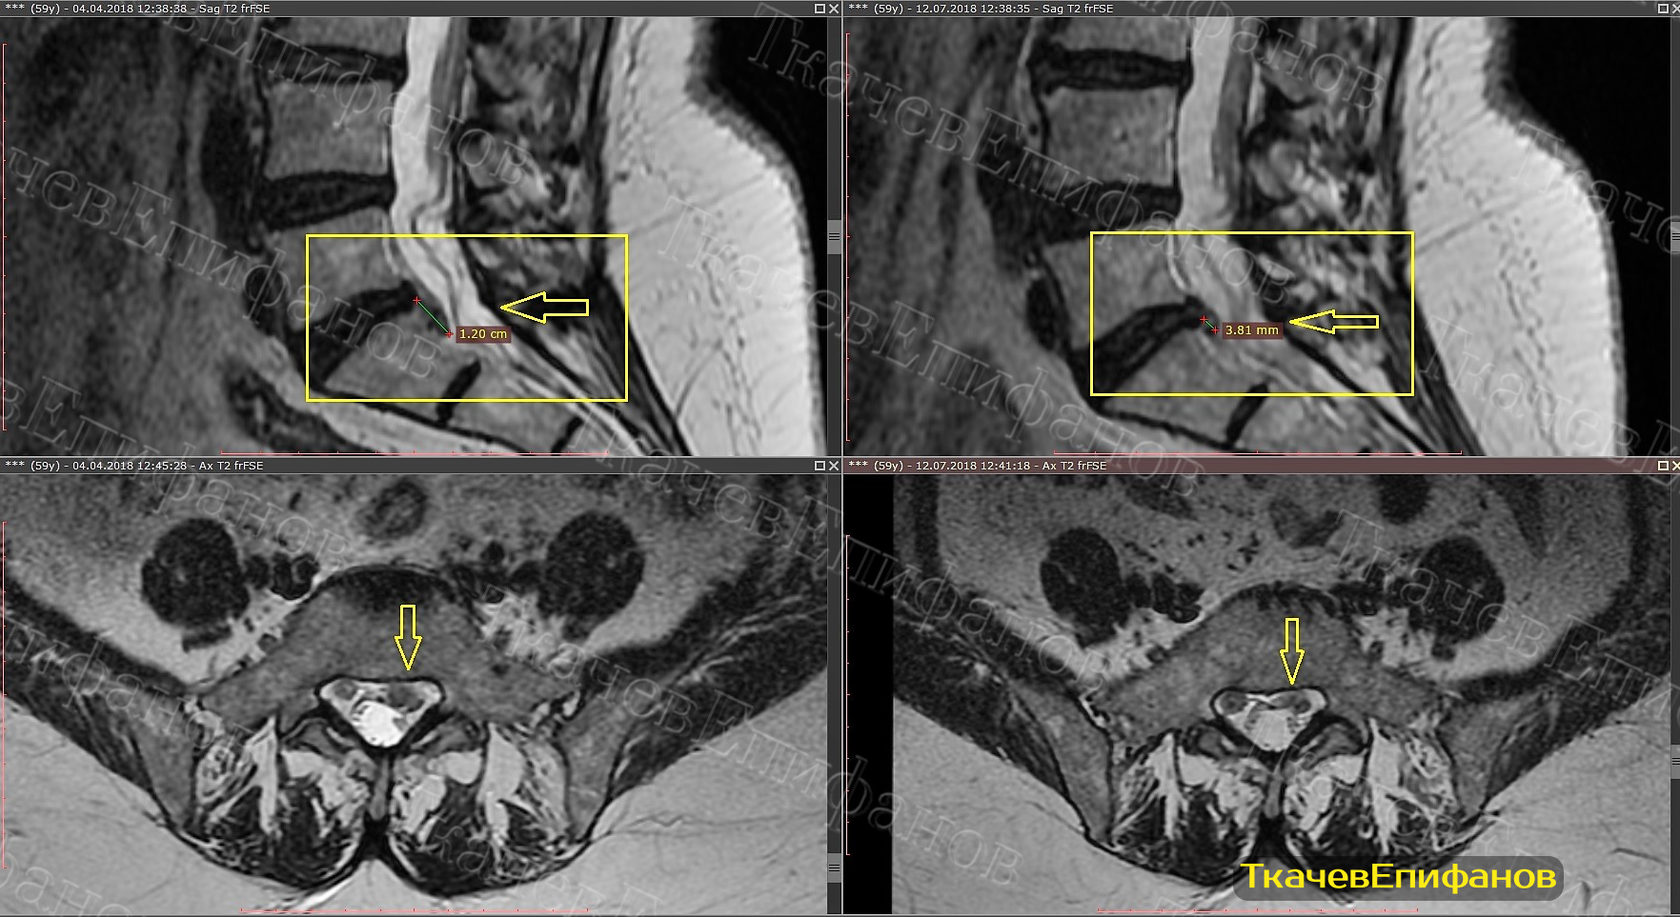

Каудальная миграция диска l4 l5

Каудальная миграция диска l4 l5 113 фотографий